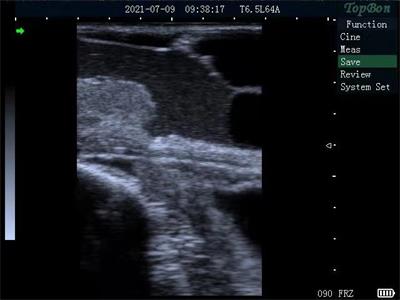

The New Hiyi THY8 High-end Full Waterproof Digital B-Ultrasound is high-quality instruments, which is with 8 inch medical ultra-clear display screen, bigger and clearer. The whole machine is fully waterproof and dustproof. It supports multiple probes. And the probe is fully waterproof. It has optional video glasses with large capacity of lithium battery. Meanwhile it has Chinese touch keys, and also has a variety of animal measurement software package.

HiYi Veterinary Ultrasound THY8 High-end Full Waterproof Digital B-Ultrasound Diagnostic Instrument For Cattle Camel Images |